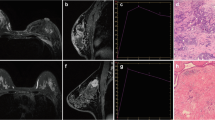

Magnetic resonance imaging (MRI) equipment used was a Philips Achieva 1.5 T MRI scanner with a dedicated bilateral breast coil. Patients were placed in the prone position, and both breasts were naturally suspended inside the hole in the center of the coil, without compression. The patients were asked to breathe softly and remain motionless. A venous channel was established in advance in the upper arm of each patient, and a long indwelling catheter with a three-way junction was implanted. The two other ends of the three-way junction were connected to 20 ml normal saline and 0.1 mmol/L/Kg dose of contrast agent gadodiamide injection. At the same time, a dynamic scanning sequence was set, and the scanning range covered the entire breast. Six DCE-MRI scans were performed, each lasting for 90 s. First, the masking film was scanned (the first scan). The patient was asked to remain in the original position, and the interval between each scan was 30 s. After the scanning was suspended, a bolus of contrast agent (injected at a speed of 2.5 ml/s, and then 20 ml bolus of normal saline) was injected using a high-pressure syringe. After the suspension was concluded, the scans were performed five times consecutively. The duration of each 3D dynamic sequence scan was 90 s, and the total duration of dynamic enhancement was 9 min. The maximum diameter line and three-dimensional volume of the tumor body were measured using DCE-MRI and magnetic resonance diffusion-weighted imaging (DWI), respectively, and reflected the size and volume of the lesion. On DCE-MRI, the region of the tumor with obvious enhancement (avoiding the necrotic area) was selected as the region of interest, and a time–intensity curve (TIC) was drawn. TIC is an indicator reflecting the microvascular density and vascular permeability of the tissue, and is divided into three types: type I is the inflow type, that is during the dynamic acquisition time, the signal curve shows a continuous and slow increase; type II is the platform type, that is during the dynamic acquisition time, the signal curve begins to rise significantly, and then remains flat; and type III is the outflow type, that is during the dynamic acquisition time, the signal curve begins to rise significantly, and then decreases significantly. DWI was used to analyze the tissue structure and internal characteristics based on the diffusion of water molecules in tissue cells. This method not only provides morphological information of the tumor but also helps evaluate the efficacy by measuring the apparent diffusion coefficient (ADC) of the tumor before and after chemotherapy.

In this study, we combined physical examination, color Doppler ultrasound, and MRI to evaluate neoadjuvant therapies; the combined method is referred to as triple the evaluation method. Baseline evaluation was conducted before treatment. The efficacy was evaluated by physical examination and color Doppler every cycle, and the efficacy was evaluated by physical examination, color Doppler, and MRI every two cycles. Specific evaluation methods were as follows: (1) complete response (CR): ① all the target lesions disappeared completely under physical examination, color Doppler ultrasound, and MRI; ② the mass was visible under color Doppler ultrasound or MRI; however, the time signal curve of MRI changed from outflow or inflow to the platform, and it repeated continuously twice. (2) Partial response (PR): ① physical examination and imaging examination indicated tumor shrinkage; ② there was no change in tumor size, and one of the following conditions was met: A. the tumor became softer on physical examination than that in the previous cycle; B. the ultrasonic echo changed from a low echo to a leaning low echo and equal echo; C. the blood flow signal of the ultrasonic image changed from rich to medium, small, and then to no blood flow signal; D. MRI enhancement degree decreased; E. MRI time signal curve changed from outflow to inflow to platform. (3) Progressive disease (PD): ① the tumor is enlarged; ② there is no change in the tumor size and one of the following conditions is met: on physical examination, the tumor has become harder, the ultrasonic blood flow is richer than that in the previous cycle, the intensity of MRI has increased, and the time blood flow curve changes from inflow or outflow to the platform. (4) Stable disease (SD): the lesion size showed no change between that of PR and PD.

We used multiple logistic regression analysis to analyze the correlation between the clinical evaluation parameters and final pathology. The b value was used to judge the influence of factors on postoperative pathology and the OR value was used to judge whether the research factor was a protective factor or a risk factor. Based on the analysis, the increase in ultrasonic blood flow after treatment had an impact on pathology; the value of b was 2.561 and the value of OR was 12.949, which is a risk factor for failure of chemotherapy. The presence of two preoperative time–signal intensity curves is a therapeutically effective protective factor for inflow. The value of b was −2.622 and the value of OR was 0.073, which is a protective factor for effective chemotherapy (Table 2).

In this paper, we only discuss imaging evaluation methods, wherein, MRI mainly reflects the efficacy of NAT in breast cancer based on the characteristics of lesion morphology and size, dynamic contrast-enhanced semi-quantitative or quantitative parameters, ADC values, and magnetic resonance spectroscopy (MRS) [16,17,18]. In addition, due to the tumor cell death and reduced cell density, breast cancer patients who are in remission after NAT also present with reduced DWI signals and increased ADC values [19]. At present, multi-parametric MRI (mpMRI) imaging omics lack unified criteria for the selection of different sequence omics, which limits its technical promotion [20, 21]. The traditional mono-exponential model diffusion-weighted imaging (mono-exponential-DWI) is an imaging method for calculating the voluntary movement of water molecules in the tissue gap using a single exponential function. ADC is the most commonly used clinical parameter, reflecting the degree of tissue limitation. The pathological mechanism of applying ADC values to breast tumors is that the proliferation of tumor cells leads to an increase in cell numbers, disorder of tissue structure, and reduction of extracellular space, resulting in the limitation of water molecule movement in the intercellular space of the tissue, increase in DWI signals, and decrease in ADC values. Therefore, there was a significant correlation between ADC values and cell density. At present, however, the correlation between different molecular subtypes and ADC values remains unclear. However, according to several studies, the ADC values of different molecular subtypes are different [22,23,24,25,26,27], and there is no consensus on the best b value of breast DWI. This study further verified the predictive effect of enhanced MRI findings on the outcomes of neoadjuvant therapy. In this study, we found that the therapeutic effect of neoadjuvant therapy can be better evaluated by combining clinical physical examination, color ultrasound, and nuclear magnetic resonance evaluation. The three methods complement each other to avoid the insufficient evaluation of a single method, which is convenient for the majority of prefecty-level hospitals to carry out. In addition, the method is simple and feasible and suitable for promotion.